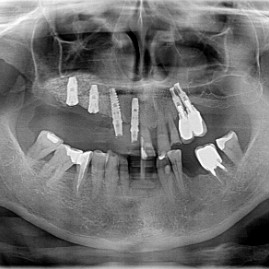

Lat 50, pół roku przed rozpoczęciem leczenia implantologicznego przestał palić papierosy. Znacząca poprawa higieny, pacjent silnie zmotywowany. Po regeneracji kości i rekonstrukcji tkanek miękkich odbudowa sześciu zębów na koronach porcelanowych. Na zdjęciu widoczna ilość i jakość tkanki kostnej po rekonstrukcji. W porównaniu ze stanem początkowym uzyskano znaczącą poprawę warunków kostnych nie do osiągnięcia metodami sterowanej regeneracji kości z użyciem reklamowanych markowych błon kolagenowych i dosypaniem kości z butelki.